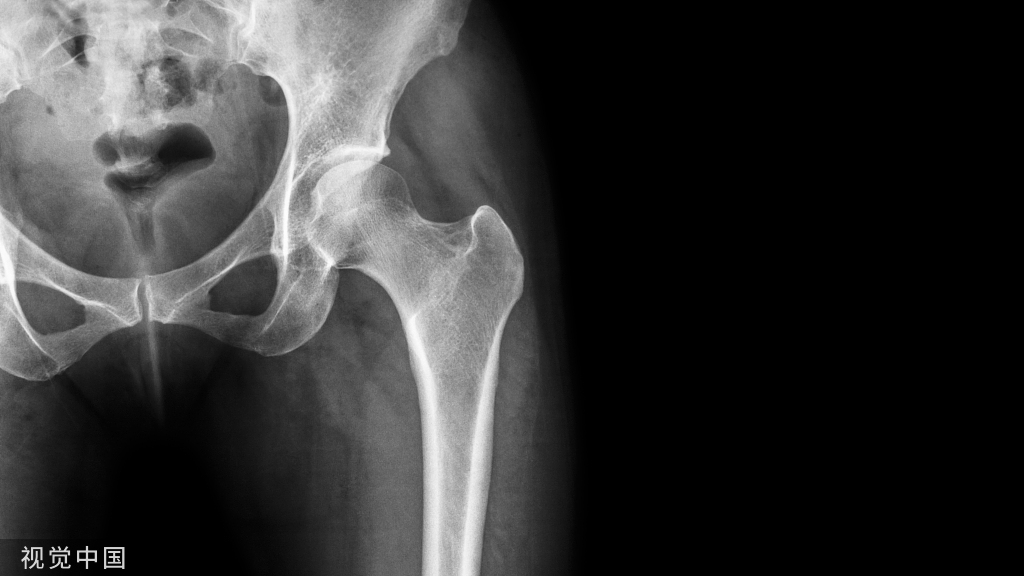

1、确定下肢关节的中心点(1)髋关节中心髋关节中心点由股骨头来确定,由于股骨头是相对比较规则的圆形,使用Mose圈或圆规就能确定股骨头中心也就是髋关节中心。

4、画出与机械轴相关的角度股骨近端外侧角(LPFA):沿股骨头中心与大粗隆最高点划一直线,连接股骨头中心与膝关节中心划一直线(机械轴),两者之间形成的外侧夹角,正常为90°±5°。